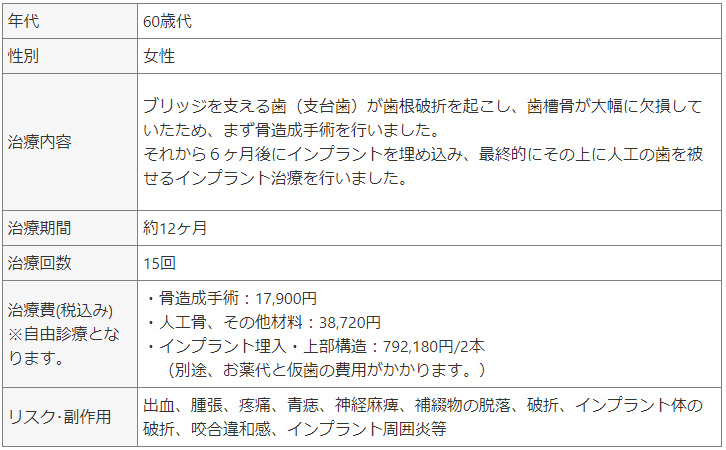

インプラント治療(インプラント治療は自由診療であるため、原則保険の適用はされません。)

インプラント治療は、歯を失った方に対して顎の骨にチタン製の人工歯根(デンタルインプラント)を埋入し、咬合の再建を行う治療です。

インプラントのメリットは、他の歯に依存せずに単独で機能するため、周囲の健康な歯を削る必要がありません。また、しっかりと固定されることで、入れ歯のように動いたり、外れたりする心配がありません。さらに、噛む力が強く、硬い食べ物も問題なく食べられます。見た目も自然で、自信を持って笑顔を見せることができます。

インプラント治療は、適切な診断と計画が重要です。まず、口腔内の状態を詳細に診査し、CTスキャンなどのX線検査で骨の量や質を確認します。

インプラント体を埋入する位置は、血管や神経などの解剖学的に危険な構造を避けつつ、隣在する歯との水平的な位置関係や噛み合わせのバランスを加味しながら決定されます。

最新の3Dシュミレーションソフトを用いて解析を行い、この解析データを元に手術用ステントを作製し、専用ドリルを用いて手術が行われます。

骨が十分でない場合:

骨移植やGBR、サイナスリフトなどの骨造成手術が必要になることもあります。骨造成手術は、骨が不足している部位に骨を補充する手術です。骨が不足しているとインプラントの固定が不十分になり、治療の成功率が低下するため、骨造成によって骨の量を増やし、安定した基盤を作ることが必要です。

骨造成手術には、主に自家骨移植や代用骨またはこれらを組み合わせる方法があります。

自家骨移植は患者さん自身の骨を使用する方法で、拒絶反応が少なく、骨を作る能力が高い特徴があります。

人工骨移植は合成材料を使用する方法で、骨の供給が無制限ですが、自家骨に比べて骨を作る能力が劣ります。

患者さんの状況にあわせて最適な骨造成手術を選択します。

症例① 歯根破折のため左臼歯部を抜歯しインプラント治療を行なった治療例。